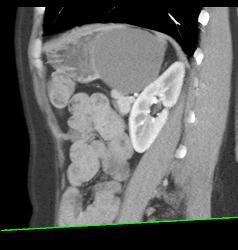

Gastric Duplication Cyst